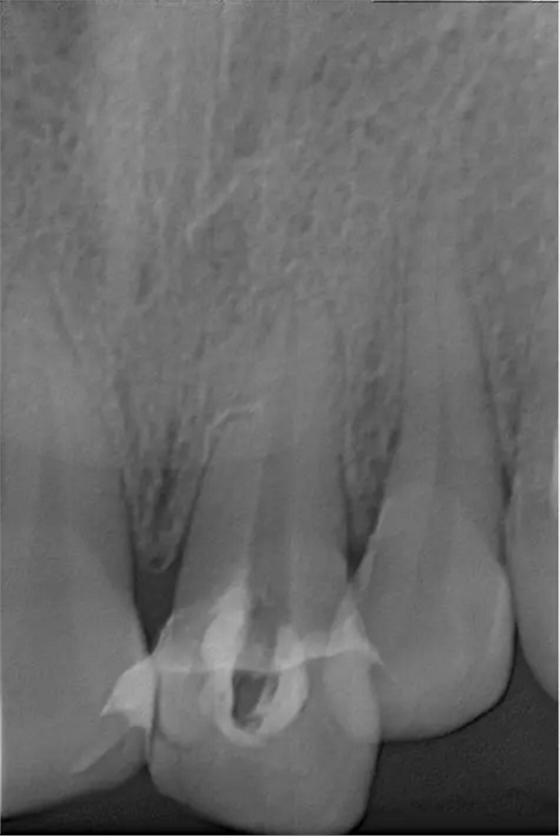

翻瓣去除側(cè)穿超出的牙膠尖

術(shù)后縫合

術(shù)后片